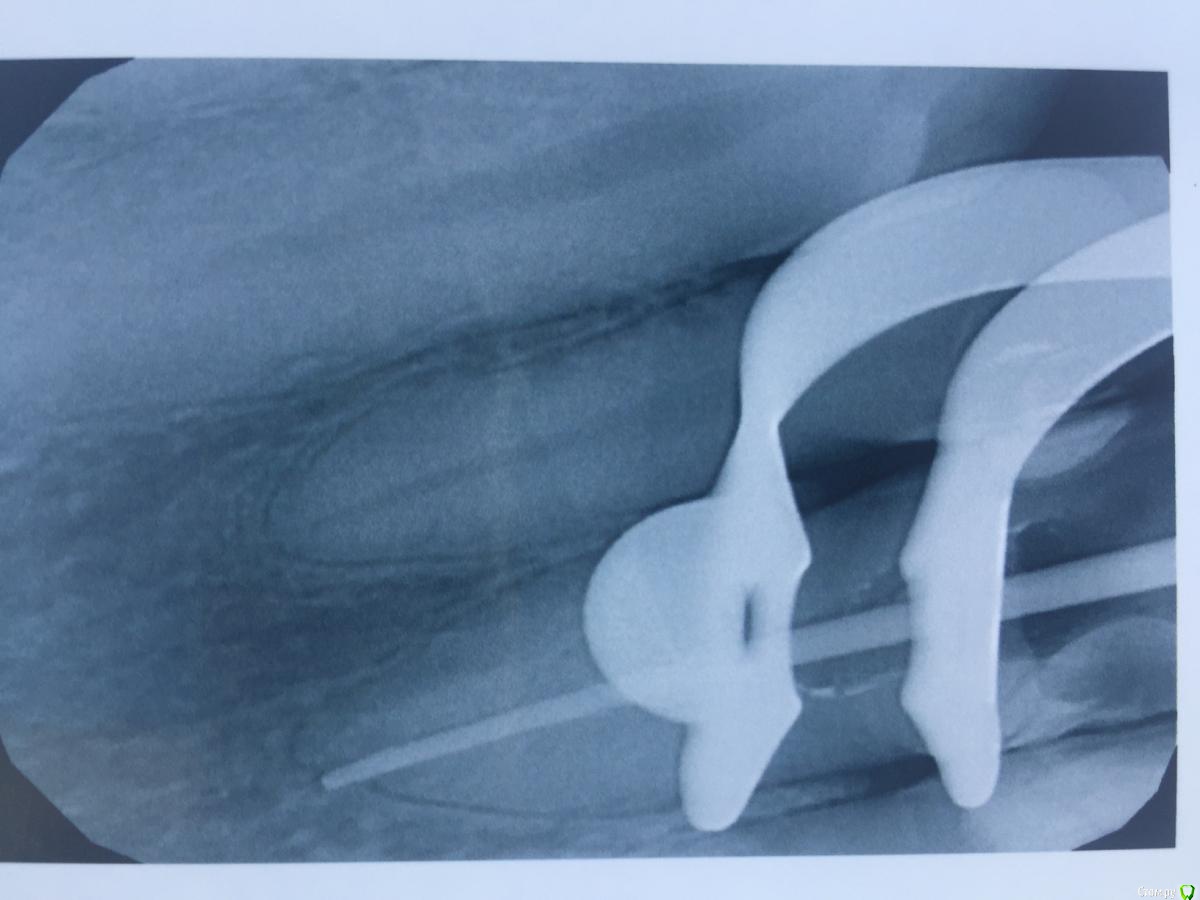

alina39 Опубликовано 9 декабря, 2016 Автор Поделиться Опубликовано 9 декабря, 2016 (изменено) Сделали новую КТ, подтвердился диагноз кистогранулема, почти киста по размерам.В прикрепленных - скриншот кт зуба.А главное боль не проходит, промыли и кальций положили неделю назад а боль не унимается, болит как рана и изредка дергает немного.Был один светлый период - 3 недели назад - когда зуб открыли, сказали полоскать и он неделю после этого не болел совсем, а потом все по новой. Изменено 9 декабря, 2016 пользователем alina39 Ссылка на комментарий

alina39 Опубликовано 9 декабря, 2016 Автор Поделиться Опубликовано 9 декабря, 2016 (изменено) покажите снимки на стадии леченияДругих снимков нет, сначала делали рентген, но на нем кисты не было видно, и потом вот два КТ: первый скриншот - это КТ 3 дня назад, а два других - 3 недели назад. Изменилось ли что-то за эти 3 недели? Изменено 9 декабря, 2016 пользователем alina39 Ссылка на комментарий